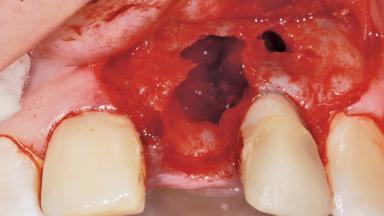

Late Placement of an Implant in a Maxillary Left Central Incisor Site

Bone Augmentation Horizontal|Staged

Augmentation Materials Xenogenous|Membrane

Bone Volume Deficient horizontally, requiring prior grafting